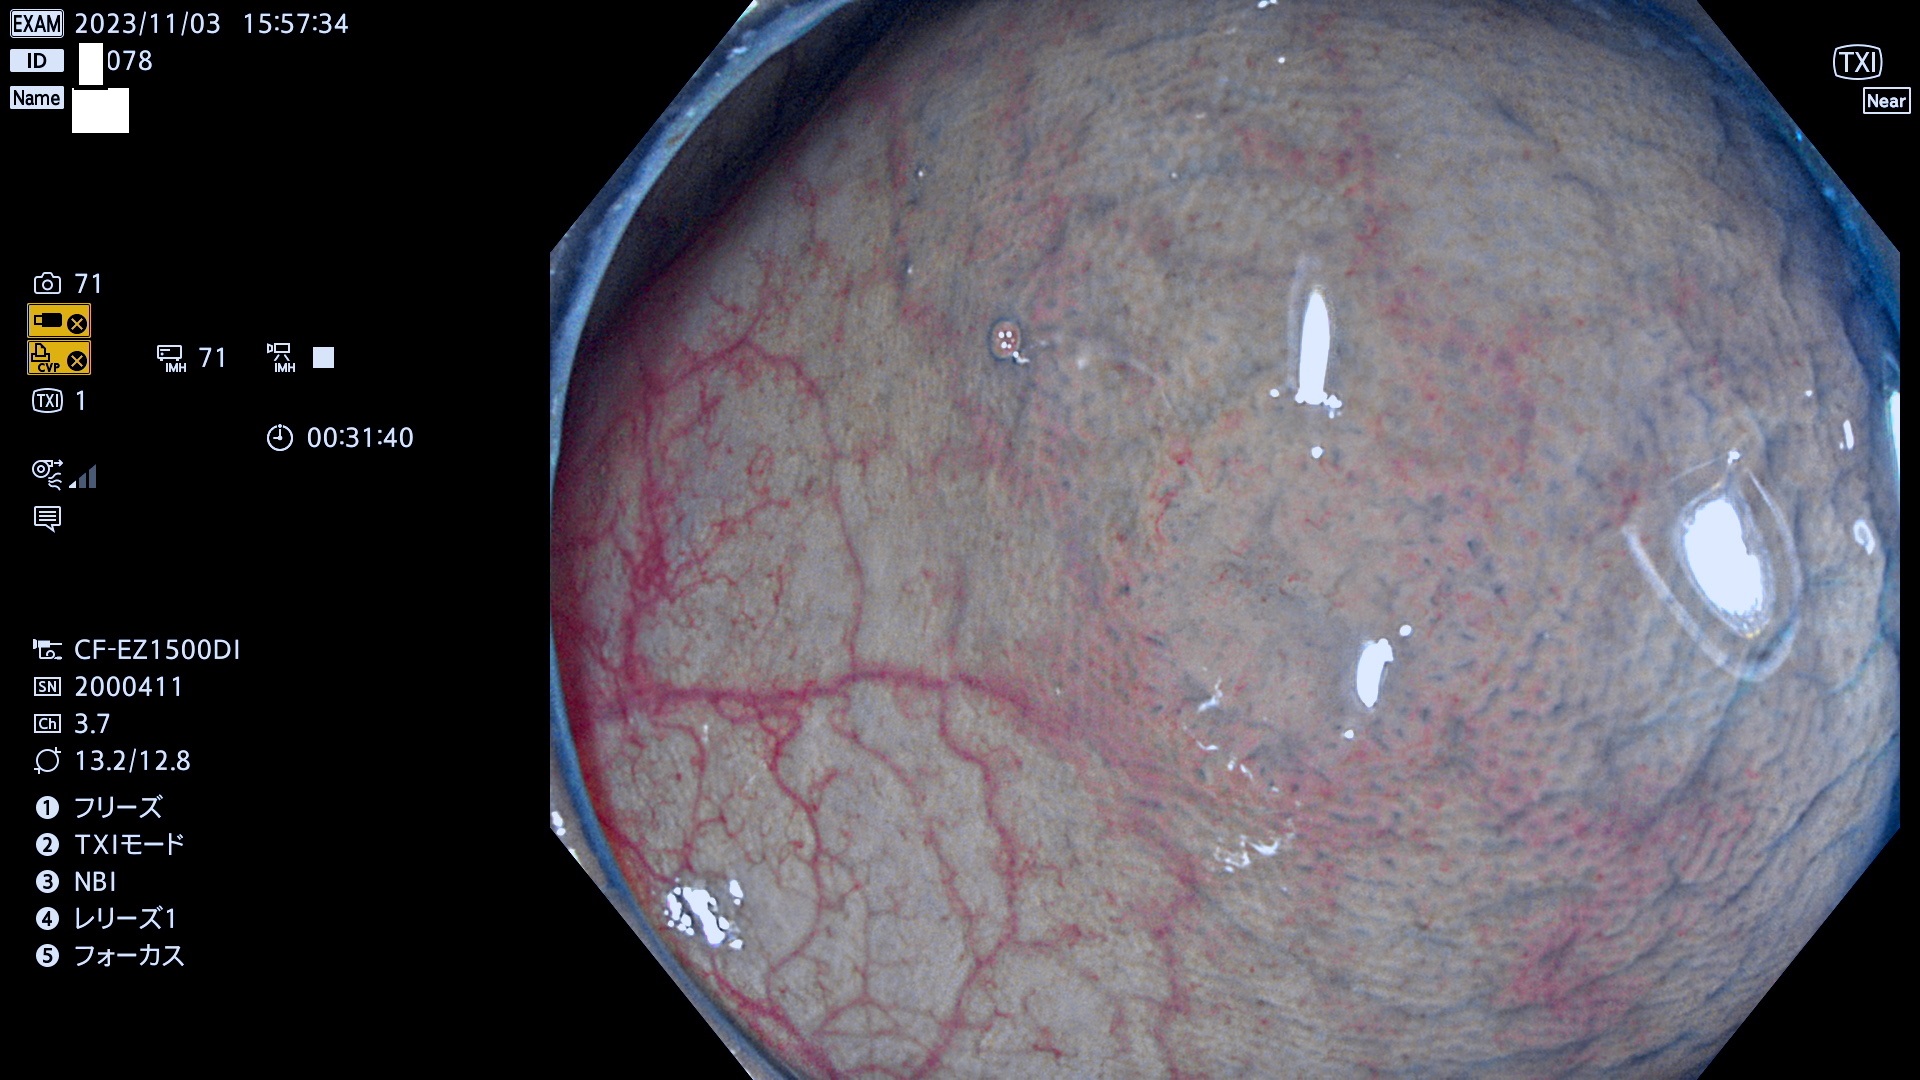

表面型腺腫(Flat Adenoma)の中で、完全に平坦な物をUb、陥凹している物をUcと呼びます。平坦隆起型(Ua)よりも、発見が難しく危険な病変です。このタイプは「内視鏡後・大腸癌の重要犯人」であり、この発見率は「腺腫発見率」よりも、重要な意味があります。

毎週の検査(木・金・土・日)に発見されたUb、Uc型・腺腫を、その週の日曜の夜にUPし1週間、提示します。

抽出の対象期間 2023年11月2日(木)〜11月6(月)の5日間(60件の検査)11件